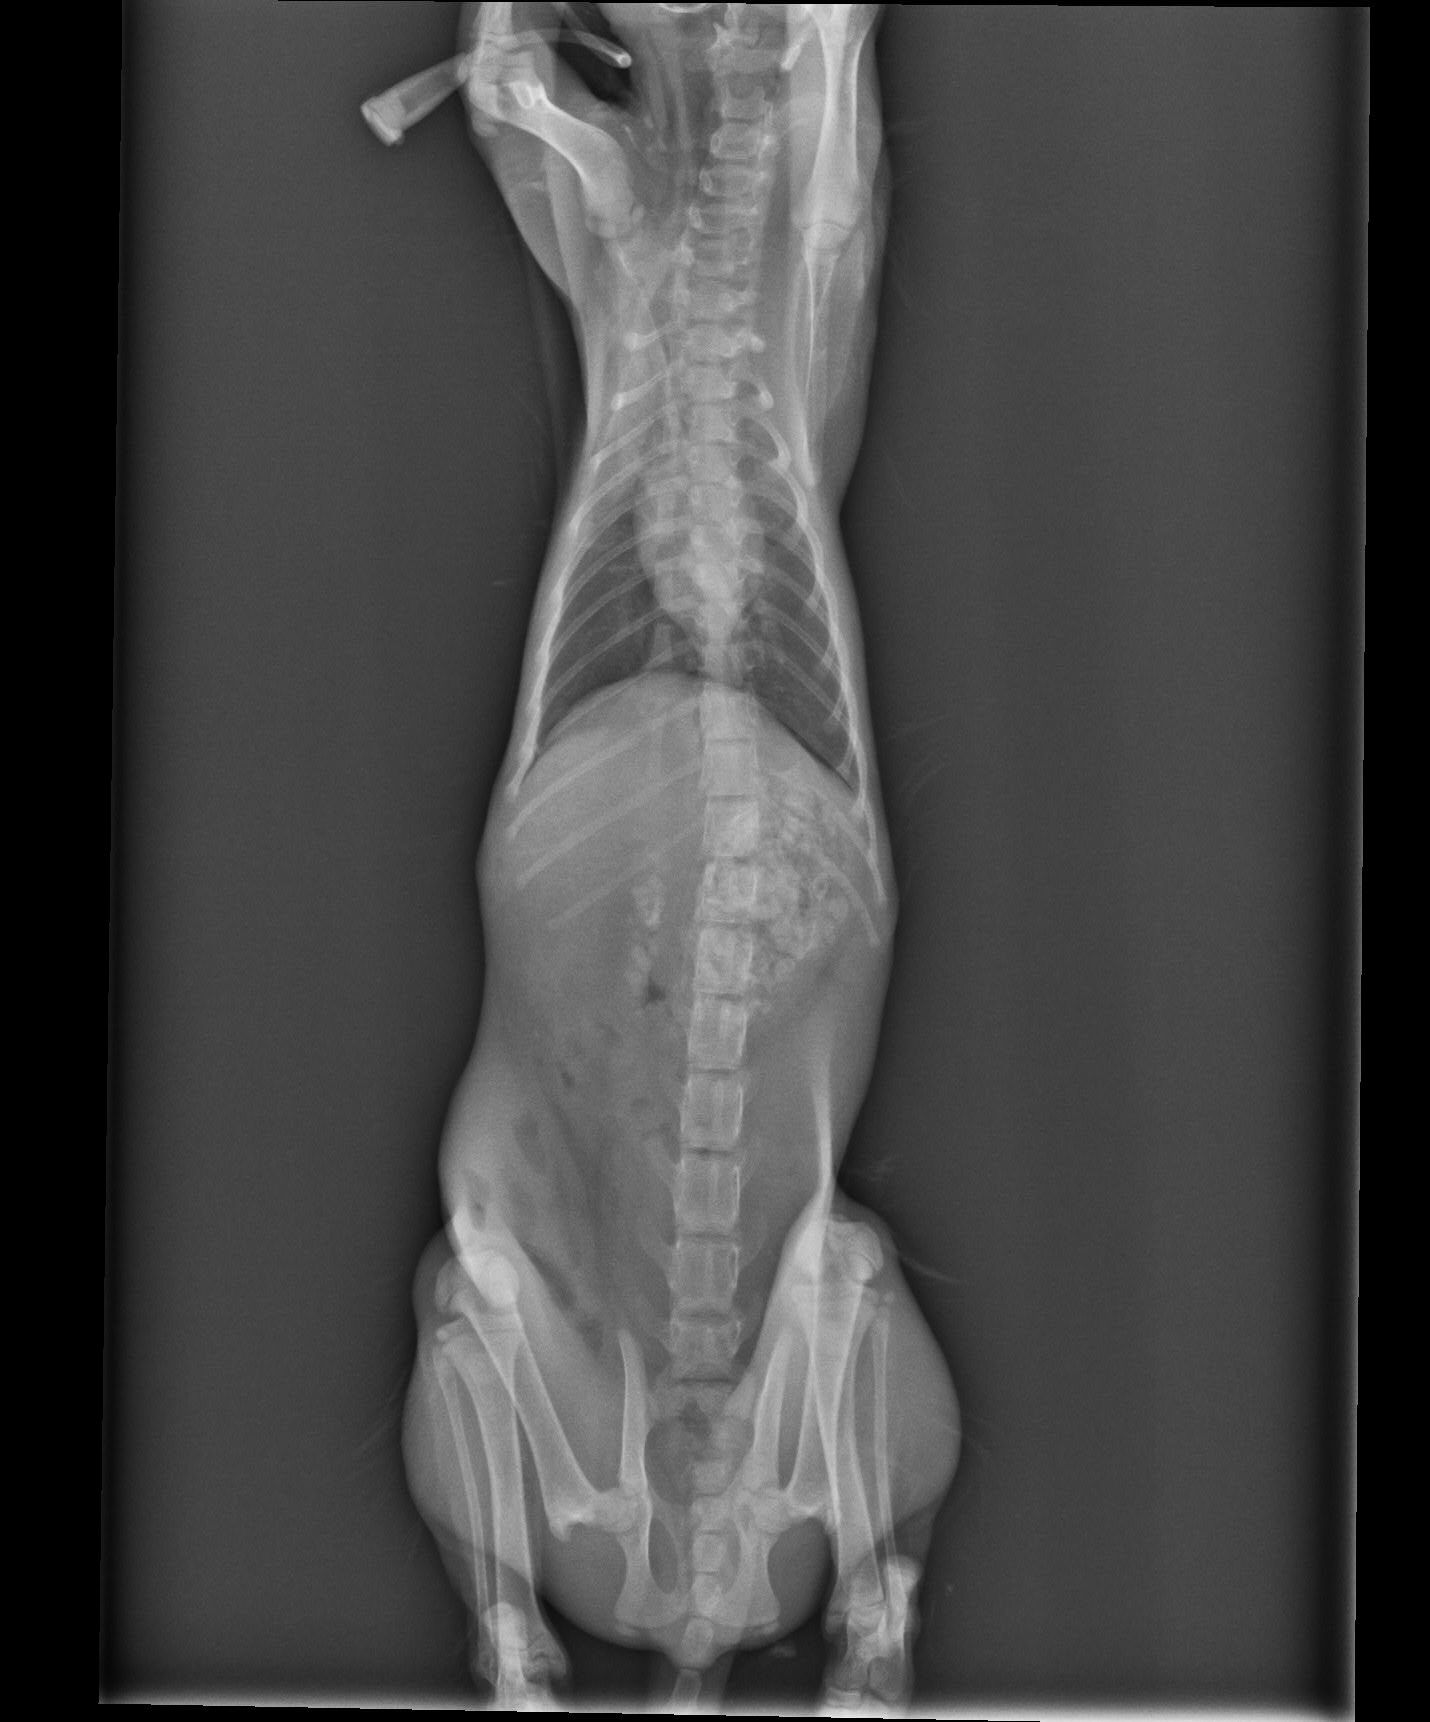

主題: 被車撞到的小貓平安 申請者姓名: 梁仕宏 花色: 申請日期: 2020-05-15 15:12:04 申請者部落格: 申請者臉書網址: 梁仕宏 所在縣市/合作醫院: 高雄市/小新動物醫院 治療費用: 5000元 需求人數: 22人 已結案 (2024-05-31 18:16:25) 報名人員: philtery x10(已付款)、艾曼達、艾曼達 x7、艾曼達 x4(已付款)、粉圓(已付款)、派派 x5(已付款)、superwu、superwu(已付款)、Candice(已付款)、 候補人員: 動物病情說明: 安安是隻約三個月大的小賓士,可能是年紀太小不會過馬路,又或是因騎士沒注意而撞到牠,牠被撞後緊張逃進路邊診所,好心的工作人員洽好是社團貓友因而在社團求援,由於案發地在我家附近,通報時間又是4月13日晚上近9點,時間非常緊迫,怕醫院近關門時間,所以我立刻到現場救援並聯絡醫院等我將牠送醫。 動物近況說明: 安安在醫院積極幫忙治療下,經過兩三天已脫離險境,身體狀況也好轉,但醫院再次觀察她,卻發現可能因為車禍關係產生赫尼亞現象,建議第一階段住院完成後休養2-3週再進行腹腔修補手術。在她住院期滿先行出院安置期間,她變的非常可愛親人,中途點也幫她洗澡整理,也積極幫她找家。非常值得慶幸的是,有好心的家庭願意認養,而且她的赫尼亞現象也持續改善,所以再帶她回醫院複診,確認修補手術可合併日後結紮一起進行。感謝協會,醫院,大家的幫忙,讓她度過被撞可能失去生命的難關,找到她未來的幸福。